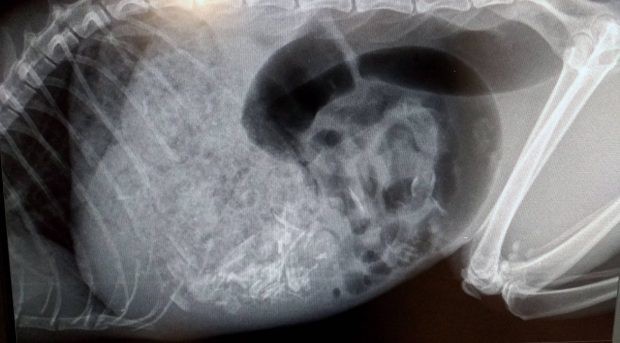

Bác sĩ Leanne Honess đã trực tiếp đứng ra để kiểm tra và điều trị cho chú mèo. Bước đầu chụp X quang, Leanne tìm thấy một con chip nhỏ được gắn trên thân của Rosie, đồng thời cũng phát hiện ra một sinh vật lạ vẫn còn khá nguyên vẹn đang nằm trọn trong dạ dày của chú mèo.

Từ hình ảnh chụp X quang cho thấy dạ dày của Rosie đã bị lấp đầy bởi một con chuột vẫn còn khá nguyên vẹn.

Trong lúc đó, bác sĩ Leanne cũng đã xác định được sinh vật lạ đang "chễm chệ" trong bụng của Rosie hóa ra là một con chuột với kích thước thước khá lớn. Do bản tính háu ăn nên mèo ta đã cứ thế mà nuốt chửng cả con chuột vào bụng, khiến dạ dày ứ đầy và bụng to phình một cách bất thường.